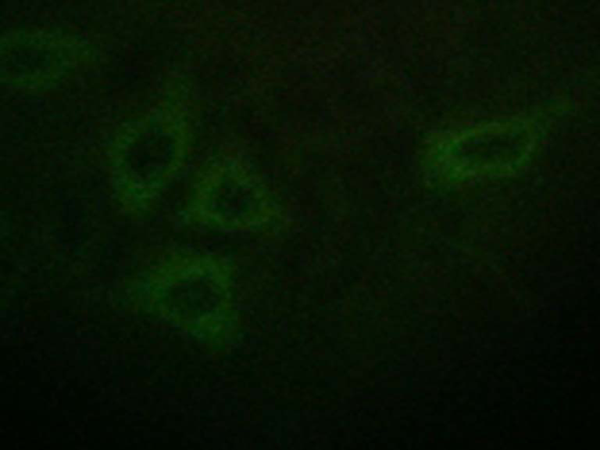

WB, IHC, IF

IF positive control:

HepG2 cells

IF Recommend dilution:

100-500